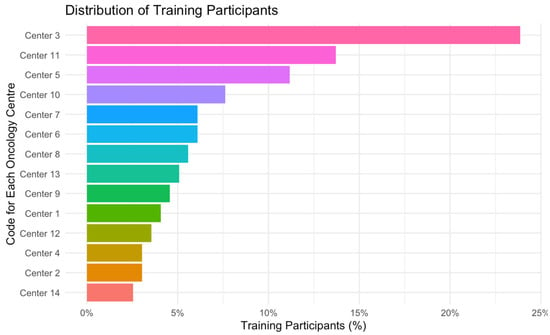

Self-Management Support for Cancer Survivors: A Descriptive Evaluation of the Symptom Navi Training from the Perspective of Health Care Professionals

by

Marika Bana, Selma Riedo and Karin Ribi

Curr. Oncol. 2025, 32(6), 326; https://doi.org/10.3390/curroncol32060326 - 2 Jun 2025

The Symptom Navi Program (SNP) is a self-management support (SMS) intervention for people with cancer. It consists of self-management supportive leaflets, educational conversations, and two standardized training sessions. A descriptive quality evaluation method was used to evaluate SNP implementation across 14 cancer services

The Symptom Navi Program (SNP) is a self-management support (SMS) intervention for people with cancer. It consists of self-management supportive leaflets, educational conversations, and two standardized training sessions. A descriptive quality evaluation method was used to evaluate SNP implementation across 14 cancer services from 2021 to 2024. We evaluated training content, methods, and participants’ confidence to use SMS in their clinical routine. Nurses, social workers, and psychologists completed ad hoc closed and open-ended questions after each training. The Work Sense of Coherence (Work-SoC) scale was used to elicit participants’ self-reported perceptions of their work context at cancer services. A series of descriptive analyses were conducted on the Work-SoC scale, the training content, and the methods. In addition, training-specific questions and predefined hypotheses were correlated. Thematic analysis was employed to examine open-ended questions. The SNP training content and methods largely met participants’ needs. Participants’ confidence in applying educational conversations decreased over time. The findings suggest a robust correlation between the application of educational conversations in daily routines and the participants’ perceptions regarding the comprehensibility and manageability of their work situations. Future research focusing on the implementation of SMS in clinical practice should examine the work context.

(This article belongs to the Special Issue Self-Management/Patient Activation and Self-Management Support Interventions for Cancer Survivors)

Figure 1